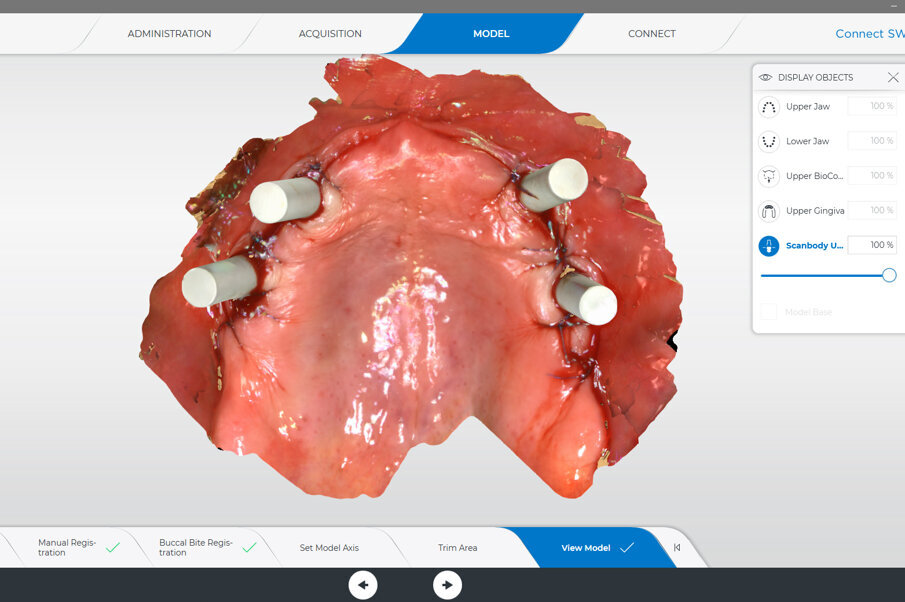

Prior to surgery, intra-oral scans of the edentulous upper jaw and dentate lower jaw were performed. The existing denture was used first as a surgical guide and then as a provisional prosthesis, after removing the palate (Fig. 4). Immediately after implant placement (Figs. 5–10), abutment position was registered with an intra-oral scan (Fig. 11). The provisional prosthesis was prepared fromthe existing denture (Figs. 12 & 13) and then the Atlantis BridgeBase was designed (Fig. 14).

Fig. 11: Intra-oral scan of the abutment position, antagonists, provisional prosthesis and jaw relation for the manufacturing of the definitive prosthesis.